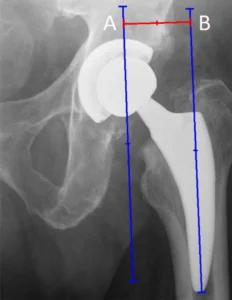

Lunghezza dell’arto e offset femorale

La radiografia post-operatoria consente una valutazione preliminare della lunghezza dell’arto operato e del ripristino dell’offset femorale. Alterazioni significative di questi parametri possono avere ripercussioni funzionali importanti, influenzando la biomeccanica dell’anca, la deambulazione e la soddisfazione del paziente.

È importante sottolineare che la valutazione radiografica deve essere sempre integrata con l’esame clinico, poiché piccole differenze radiografiche possono non essere clinicamente rilevanti e viceversa.